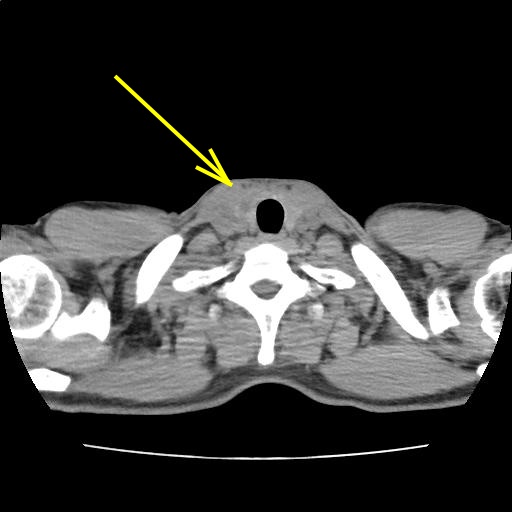

CT画像216

(214/225)